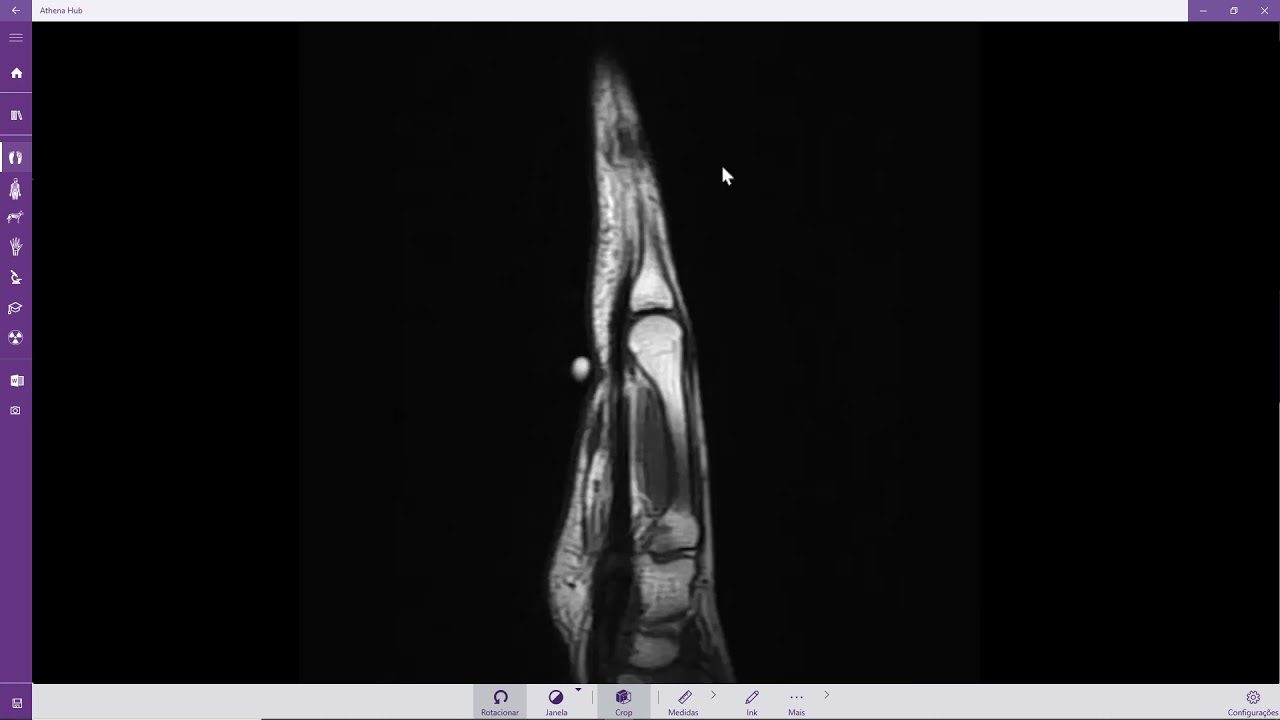

Fratura do escafóide com necrose avascular (RM)

Описание: Fratura do escafóide com necrose avascular (RM)